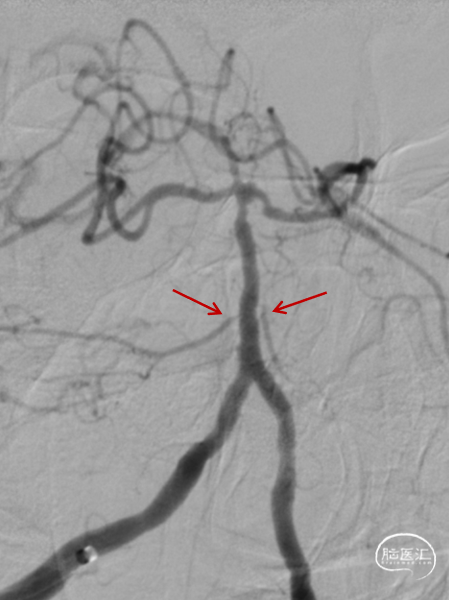

➢造影信息

造影示:右侧优势椎,经右侧椎动脉导弯造影,双侧胚胎型大脑后动脉。

基底动脉狭窄位于双侧AICA开口处,且无双侧PICA,其供血区由双侧AICA、SCA分支代偿供血。

术前DSA:双侧后交通动脉开放。